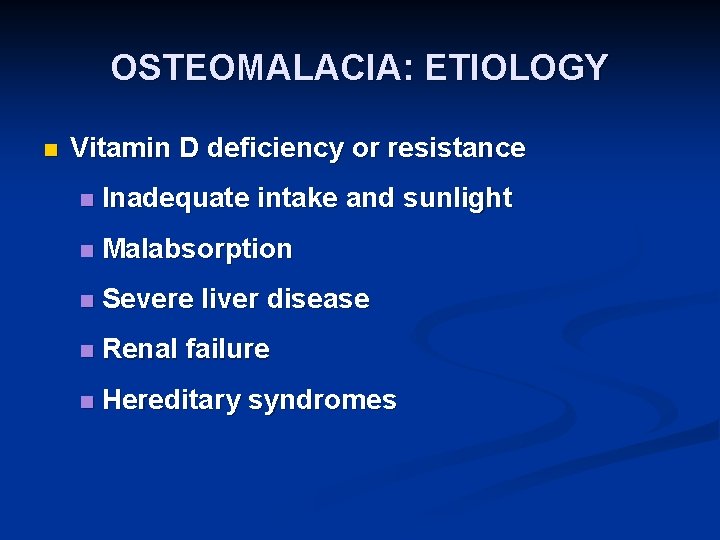

OSTEOMALACIA: ETIOLOGY n Vitamin D deficiency or resistance n Inadequate intake and sunlight n Malabsorption n Severe liver disease n Renal failure n Hereditary syndromes